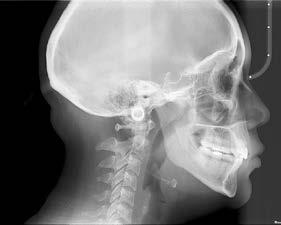

b) Análisis radiográficos, periapicales, ortopantomográficos, oclusales, lateral de cráneo, anteroposterior de cráneo.

c) Estudio y análisis tomográfico en tercera dimensión del cráneo a nivel maxilar y mandibular (Figura 24).

24.

Figura